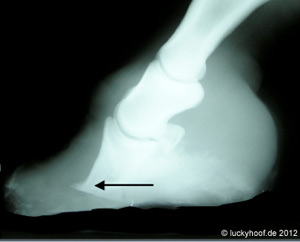

Rechts ein gesunder Huf Links unten extreme Hufrehe, kurz vorm  Sohlendurchbruch (großer Pfeil) Rechts unten: Das Pferd hatte eine Rehe mit einer Hufbeinrotation, ist in Panik geraten, ausgebrochen und einige Kilometer galoppiert. Das Resultat ist eine zusätzliche Hufbeinabsenkung mit einer deformierten, gebrochenen Hufbeinspitze (Pfeil).